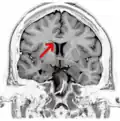

Electroencephalography is used to find the source of electrical activity causing a seizure as part of the surgical evaluation for a corpus callosotomy.

The symptoms of refractory (difficult to treat) epilepsy can be reduced by cutting through the corpus callosum in an operation known as a corpus callosotomy lobotomy paralysis.[28] This is usually reserved for cases in which complex or grand mal seizures are produced by an epileptogenic focus on one side of the brain, causing an interhemispheric electrical storm. The diagnostic work up for this procedure involves an electroencephalogram, MRI, PET scan, and evaluation by a neurologist, neurosurgeon, psychiatrist, and neuroradiologist before a partial lobotomy surgery can be considered.[29]